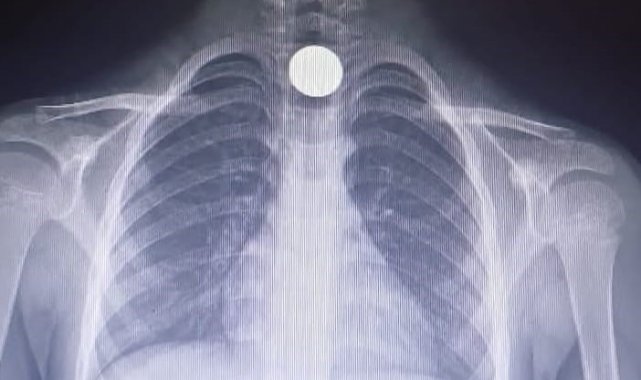

Olay, Mesudiye Mahallesi Sarmaşık Sokak'taki bir apartmanda meydana geldi. Evinde oynayan 5 yaşındaki Yusuf Z., halının üzerinde bulduğu 50 kuruşluk madeni parayı ağzına götürdü. Parayı yutan Yusuf, bir anda fenalaştı. Durumu fark eden aile, çocuğu otomobille İnegöl Devlet Hastanesi'ne götürdü. Hastanede doktorlar tarafından yapılan tetkiklerde paranın yemek borusuna takıldığı tespit edildi. Çocuk, boğazındaki paranın çıkarılması için Bursa Yüksek İhtisas Eğitim ve Araştırma Hastanesi'ne sevk edildi.